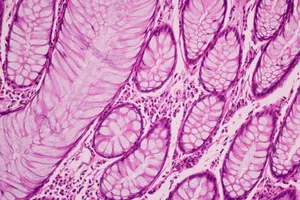

유방 결절은 다양한 원인으로 발생하며, 대부분 양성이지만 일부는 악성일 수 있습니다. 조직검사는 결절의 일부를 채취하여 현미경으로 분석하는 검사입니다.

조직검사는 채취한 조직을 특수한 용액에 담가 고정하고, 얇게 잘라 염색하는 등 여러 단계의 과정을 거쳐 현미경으로 관찰하는 복잡한 과정입니다. 병리학 전문가의 현미경으로 조직을 꼼꼼히 분석해야 하기 때문에 시간이 소요됩니다.